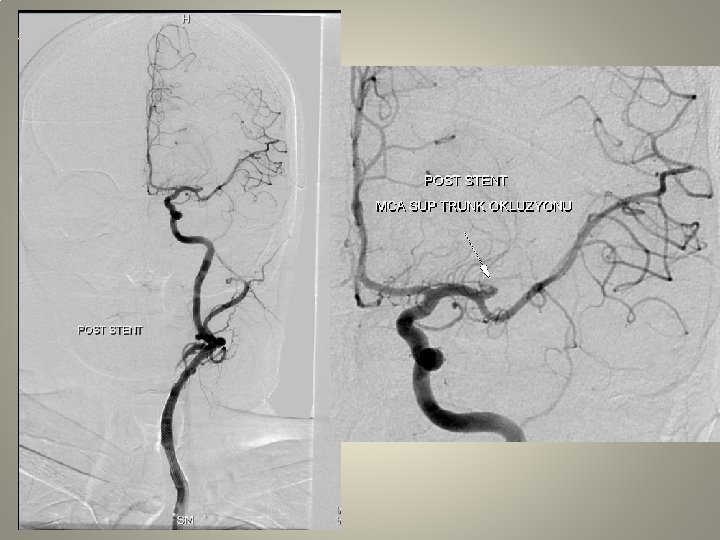

Neden stent? TANDEM lezyon

Neden stent? Distal emboli koruma

Neden stent? Eş zmanlı komplikasyon idaresi